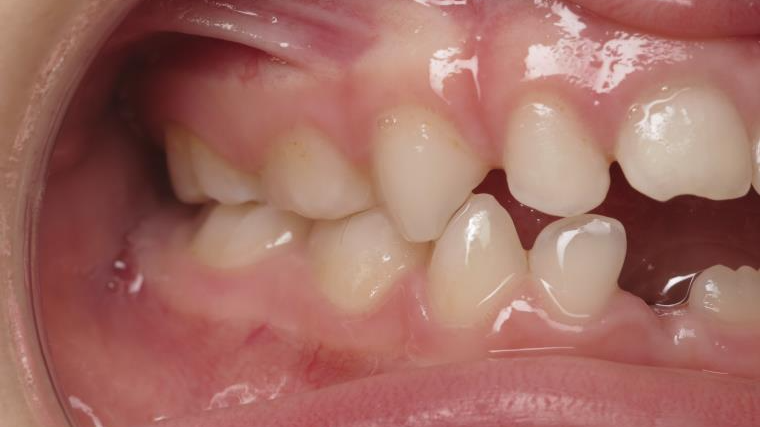

inversion postérieur coté droit et espace entre l'arcade du haut et du bas (béance)

bilan début et en cours de traitement